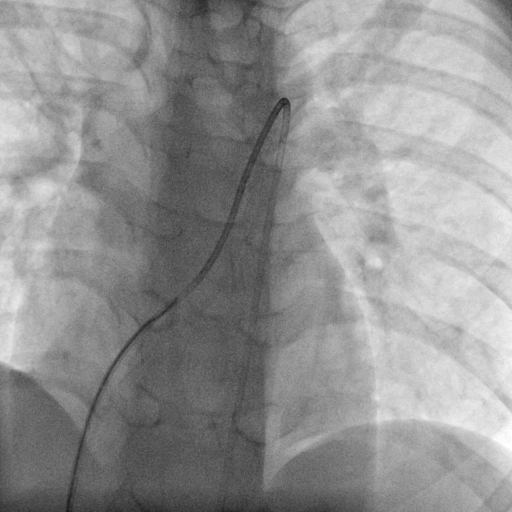

Through the femoral vein, a 5-Fr multipurpose A catheter (MP-A catheter, Cordis) was used in an attempt to cross the PDA from the MPA directly or with the assistance of a guidewire. If the antegrade approach was not successful after more than 5 minutes, operators switched to the kissing-catheter method. The antegrade catheter was left in the middle of the MPA. From the femoral artery, another 5-Fr MP-A catheter (retrograde catheter) was introduced to the descending aorta and advanced through the PDA to the middle of the MPA directly or with the assistance of a guidewire. Under a 30° cranial with 15° left anterior oblique (LAO) fluoroscopic projection, operators manipulated the antegrade and retrograde catheters simultaneously so that their distal ends would dock with each other tip to tip. A 260-cm, 0.035-inch exchange guidewire was sent from one of the catheters to another, through the docking-junction, and externalized from the proximal end of the catheter. Then, an artery-PDA-vein guidewire loop was established (Figures 1-3; Videos 1 and 2).

In all 22 patients, the artery-PDA-vein guidewire loop was successfully established using the kissing-catheter method. The average kissing-time (time from attempting to dock the 2 catheters to successfully passing the guidewire) for the guidewire rail establishment was 26 ± 15 seconds (range: 6-64 seconds). The exchange guidewire was sent from the antegrade catheter to the retrograde catheter in 15 patients, and from the retrograde catheter to the antegrade catheter in 7 patients. The average kissing-time of these 2 groups was 28 ± 17 seconds and 22 ± 10 seconds respectively, and no statistical difference was detected (t = 0.938, P = .360).

Our data confirmed the feasibility of the kissing-catheter technique: the success rate in our group was 100%, and the average fluoroscopy time for the artery-PDA-vein guidewire loop establishment was from 6 seconds to 64 seconds with an average of 26 seconds, which was acceptable in clinical practice. Based on our experience, the operative time can be further shortened as proficiency increases.